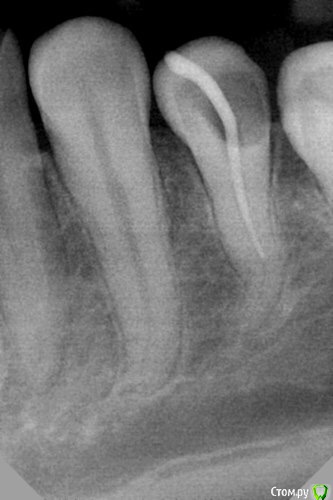

dr.Dre Опубликовано 1 апреля, 2016 Поделиться Опубликовано 1 апреля, 2016 Добрый день коллеги,прошёл данный канал до 10 дальше не идёт.Посоветуйте из своего опыта как справиться в этой ситуации? 1 1 Ссылка на комментарий

Ирина Игоревна Опубликовано 1 апреля, 2016 Поделиться Опубликовано 1 апреля, 2016 Просвет канала виден.... Попробуйте в луже из гипохлора 08 потихонечку пройти, верхнюю треть побольше расширить 1 1 Ссылка на комментарий

Ker Опубликовано 1 апреля, 2016 Поделиться Опубликовано 1 апреля, 2016 (изменено) Думаю что там два канала.Но может и ошибаюсь. Изменено 1 апреля, 2016 пользователем Ker 2 Ссылка на комментарий

Нюрок Опубликовано 4 апреля, 2016 Поделиться Опубликовано 4 апреля, 2016 Думаю что там два канала.Но может и ошибаюсь.тоже вижу здесь два корня Ссылка на комментарий